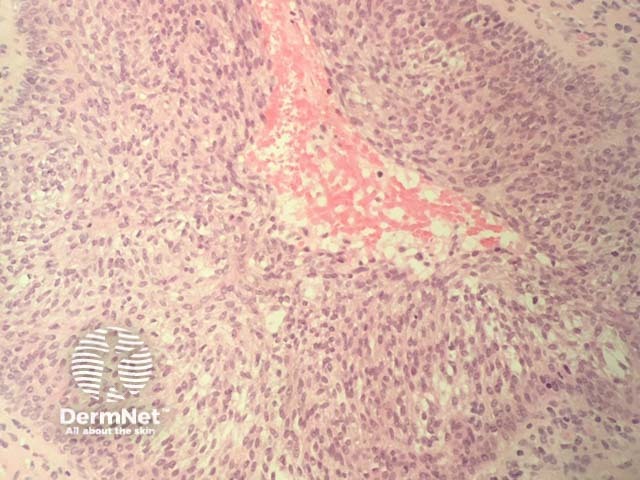

Plaque stage: as mycosis fungoides progresses, there is more obvious epidermotropism (figure 2) and a denser dermal infiltrate. There may be intraepidermal collections of atypical cells (Pautrier microabscesses, figure 3).

Figure 3